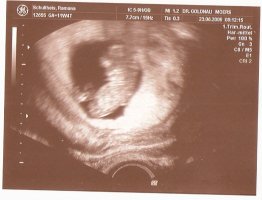

schönes Foto, sieht man sogar die beinchen ganz tol 🙂